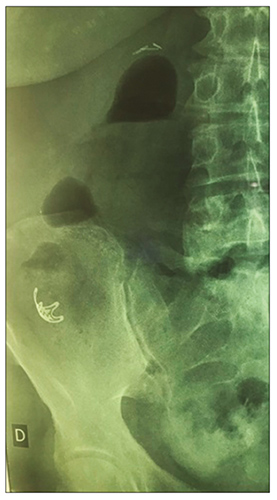

La radiografía de abdomen de control (Figura 7) no mostró signos de perforación intestinal. Egresó del sanatorio con pautas de alarma (dolor abdominal, fiebre, heces rojizas) y seguimiento ambulatorio en 48 h.